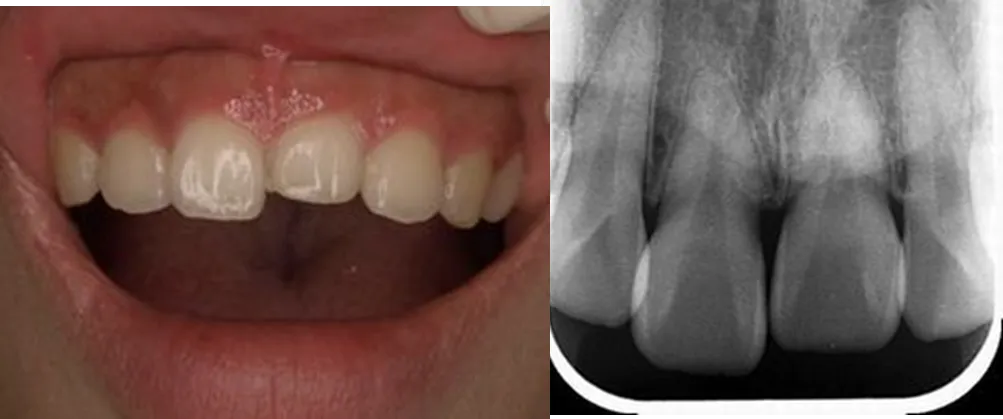

case3

Before

After

治療内容 | 右より、Zrクラウン、CTG+インプラント+Zrクラウン、ラミネートベニア(計3本修復)ホワイトニング |

治療期間 | 8ヶ月 |

治療回数 | 15回 |

リスク | 外科的な侵襲、回数や期間的な問題 |

費用(税込) | ¥1,023,000 |